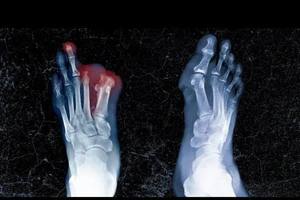

70 bệnh nhân bị nhiễm vi khuẩn lạ, không lành vết mổ nội soi ở Bệnh viện Đa khoa Quảng Trị 12/11/2025 21:19